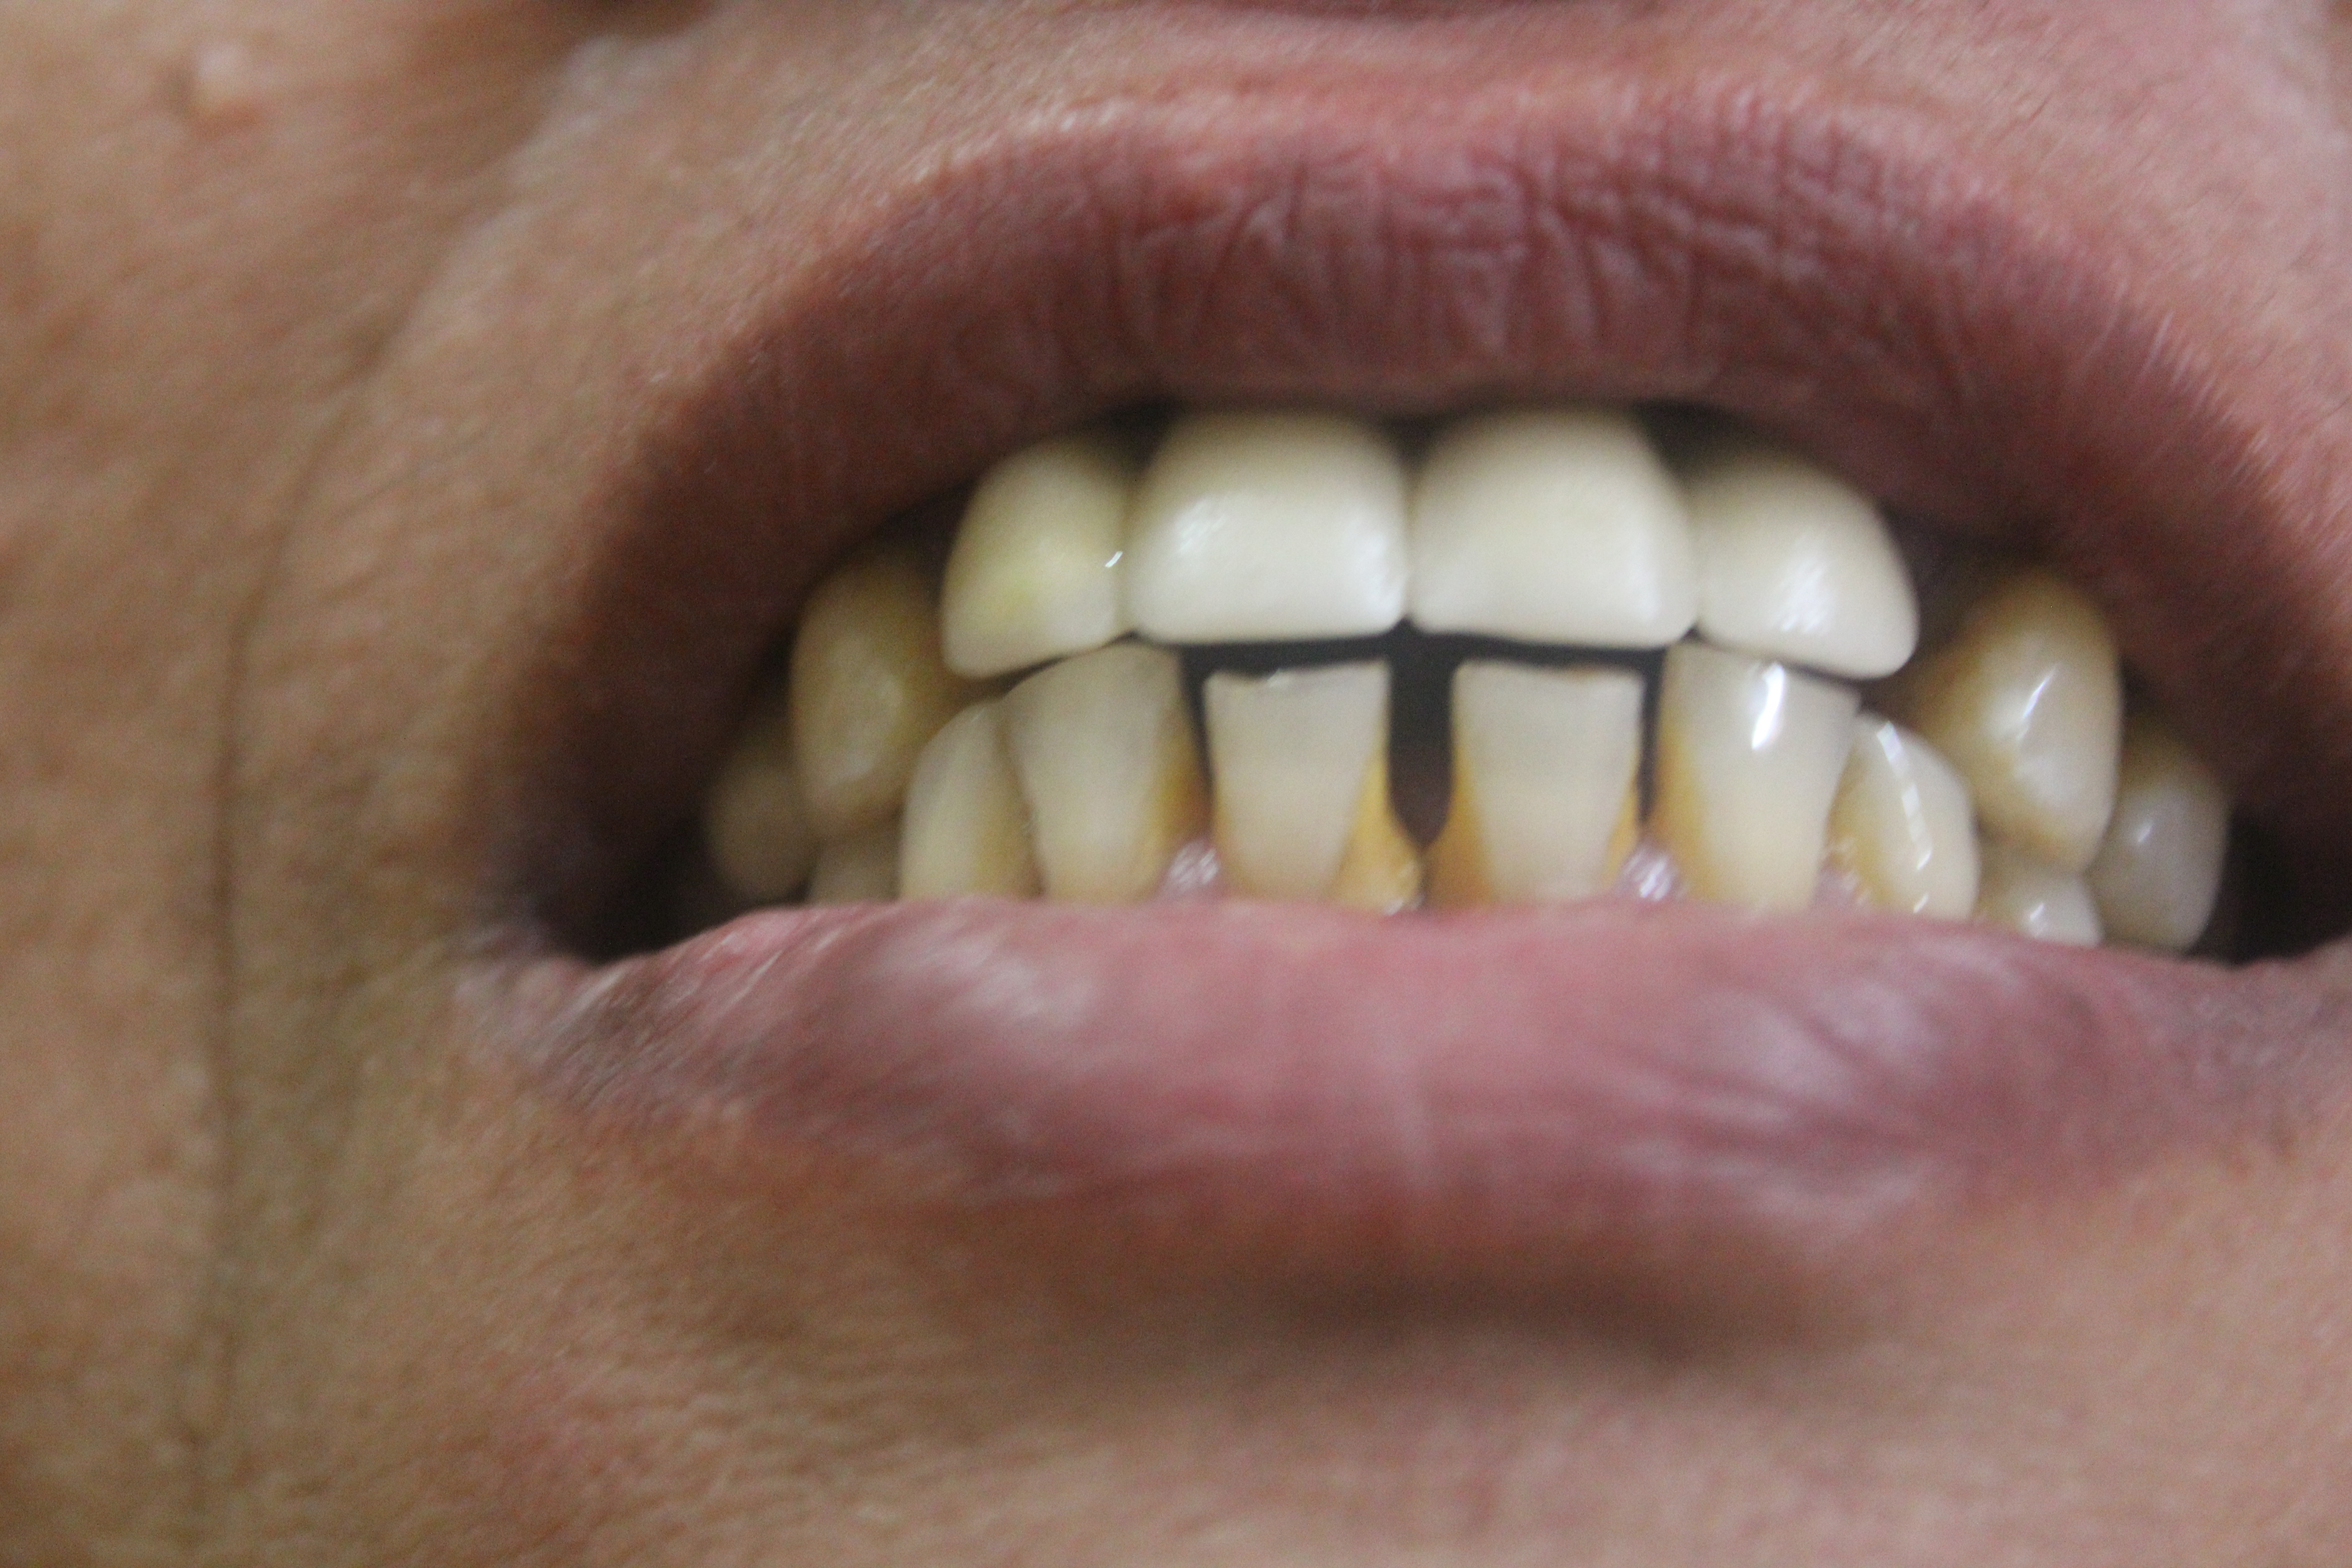

Complete Oral Rehabilitation